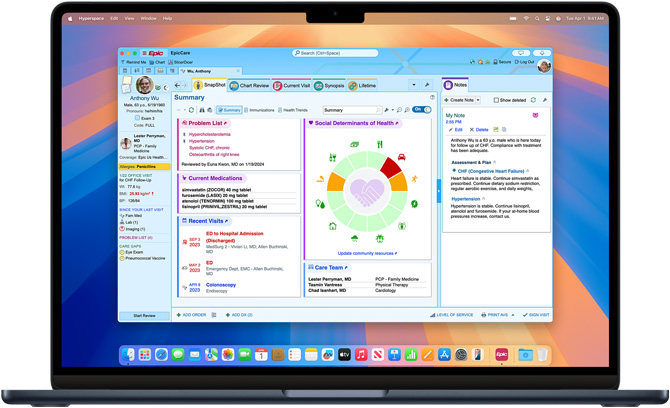

Epic Hyperspace helps providers access and update patient records quickly and easily. Authenticate using Touch ID and stay a step ahead with AI-powered clinical summaries, AI-drafted replies to patient messages, and ambient documentation technology.